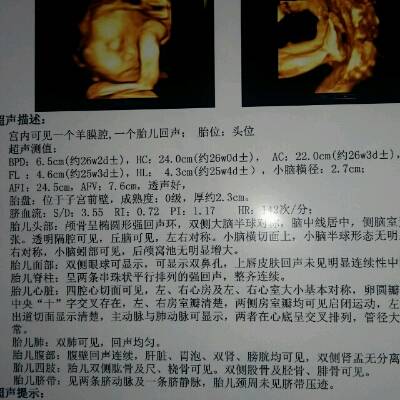

在这么多的产前检查项目中,在孕六个月左右做四维彩超是非常重要的,因为医生可以通过屏幕直观地观察到胎儿的面部、心脏、以及其他内脏器官,胎儿的所有器官在孕22周就已经发育完成,孕24周就可以清晰地看到。如果有什么异常,是可以发现的。

建议孕20周后做胎儿四维彩超。2.胎儿的四肢和主要器官在怀孕20周后已经全部发育完成。最佳检查时间为孕24周、28周,因为这个阶段胎儿结构已经形成,胎儿大小和羊水适中,胎儿骨骼回声相对较小,图像清晰。所以这个时期是胎儿畸形检测最理想的时期,通过检查可以排除大部分畸形。四位彩色多普勒超声使用的仪器称为“四维彩色超声诊断仪”。

一般来说,妊娠2428周是四维彩超的最佳时间,因为胎儿24周左右是大脑快速发育的时期,这期间胎儿结构已经形成,胎儿大小和羊水适中,在子宫内的活动空间较大,胎儿骨回声的影响相对较小,图像相对清晰。四维超声在三维超声的基础上具有实时动态效果。准爸爸和准妈妈可以通过屏幕见证宝宝在妈妈肚子里的运动、呼吸、吞咽、打哈欠、吐舌头等生理活动,非常直观。

四维彩色多普勒超声是目前世界上最先进的超声诊断技术,可以从多个方向和角度观察宫内胎儿的生长发育情况,达到最佳的检测效果,为临床诊断提供准确的科学依据。一般来说,彩色多普勒超声的异常分为两个阶段。第一阶段为ⅱ类异常,在孕1822周时进行。四维是畸胎学的第二阶段,筛查的最佳时间是孕2228周,因为这一时期胎儿的四肢和主要器官已经全部发育,羊水更适合胎儿畸形筛查。